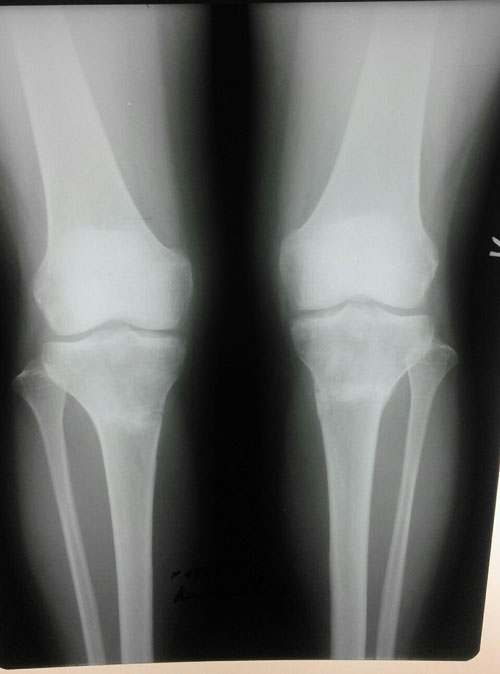

Рентген контроль и ножки в 1,5 месяца с момента снятия аппаратов.

Здравствуйте! Сращение отличное! Разрешено каблуки по нарастающей, физические нагрузки по нарастающей. Запрещено: беременеть в первые 6 месяцев с момента снятия аппаратов.

Ждём фото ножек на каблуках! Не забывайте про наш форум!